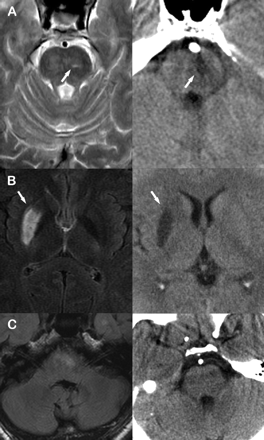

4名患者(病例2到5)PS在过程开发的;一个病人出现PS 10小时后支架(情况1)。四PSs达到最大赤字几乎在一次,和一个2小时后发病。案例1有扩大的射孔器梗塞相邻支架后的船,和例2到5没有重复新病变脑CT (图中,通过C)。

图。(A)案例1:术前先生t2加权成像(图左)显示一个小梗死(箭头)的双侧脑桥的左边区域。重复脑部CT图(右)支架植入后英航狭窄扩大显示桥的梗塞(箭头所指)。(B)案例4:术前先生fluid-attenuated反转恢复(天赋)成像(图左)揭示了权利striato-capsular梗塞(箭头所指)。重复脑部CT图(右)支架植入后对MCA狭窄(解剖)显示一个老梗塞(箭头所指),没有新纹状体外动脉增梗塞在正确的领域。(C)例5:术前天赋先生成像(图左)揭示了梗塞(左>右)双侧面积在脑桥前内侧。重复脑部CT图(右)支架植入后英航狭窄显示梗塞和新老在脑桥梗死。